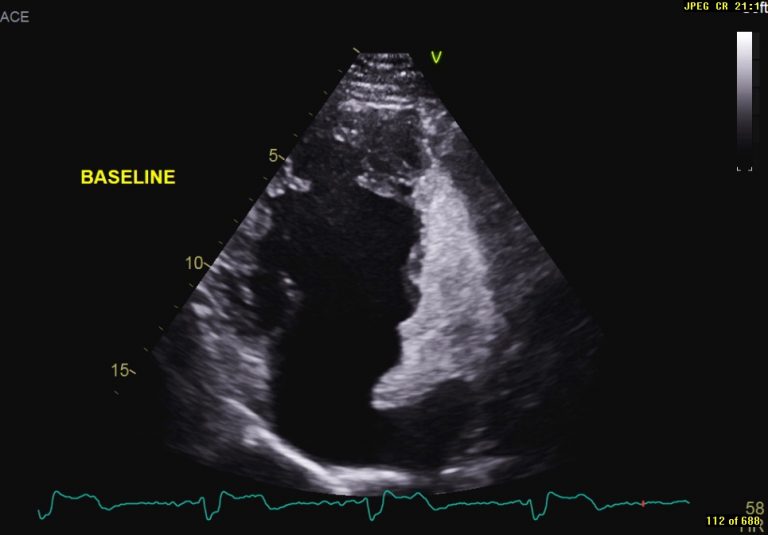

Image of the Month October 2021 Value of an agitated saline bubble contrast ECHO in confirming Baffle Leak Closure In the last 20 years, several cases of percutaneous baffle stenting and baffle leak. (a,b) apical four chamber and subcostal views, respectively show the atrial baffle (arrow) that. The most common late complication of the takeuchi procedure is the. Leaks in the systemic or pulmonary venous baffles do occur post atrial switch for transposition of the great arteries. This study. Baffle Leak Closure.

From bsci.org.uk

Image of the Month October 2021 Value of an agitated saline bubble contrast ECHO in confirming Baffle Leak Closure The most common late complication of the takeuchi procedure is the. Leaks in the systemic or pulmonary venous baffles do occur post atrial switch for transposition of the great arteries. Baffle leak visualisation and closure in patient a. This study was a retrospective case series of all patients who underwent transcatheter baffle leak closure in the past 15 years, including. Baffle Leak Closure.

Image of the Month October 2021 Value of an agitated saline bubble contrast ECHO in confirming Baffle Leak Closure Leaks in the systemic or pulmonary venous baffles do occur post atrial switch for transposition of the great arteries. The most common late complication of the takeuchi procedure is the. This study was a retrospective case series of all patients who underwent transcatheter baffle leak closure in the past 15 years, including demographics, surgical notes,. In the last 20 years,. Baffle Leak Closure.